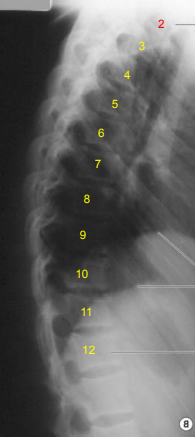

AP L-Spine: Eval Criteria

Centered at the crest (or 1.5” above) to include T12 to sacrum

No rotation

Open intervertebral joint spaces

AP L-Spine: Is this Image Good?

No.

Slight right rotation evidenced by spinous processes projected to the left of midline

T12 is clipped due to low centering at the crest

Needs collimation

Needs marker